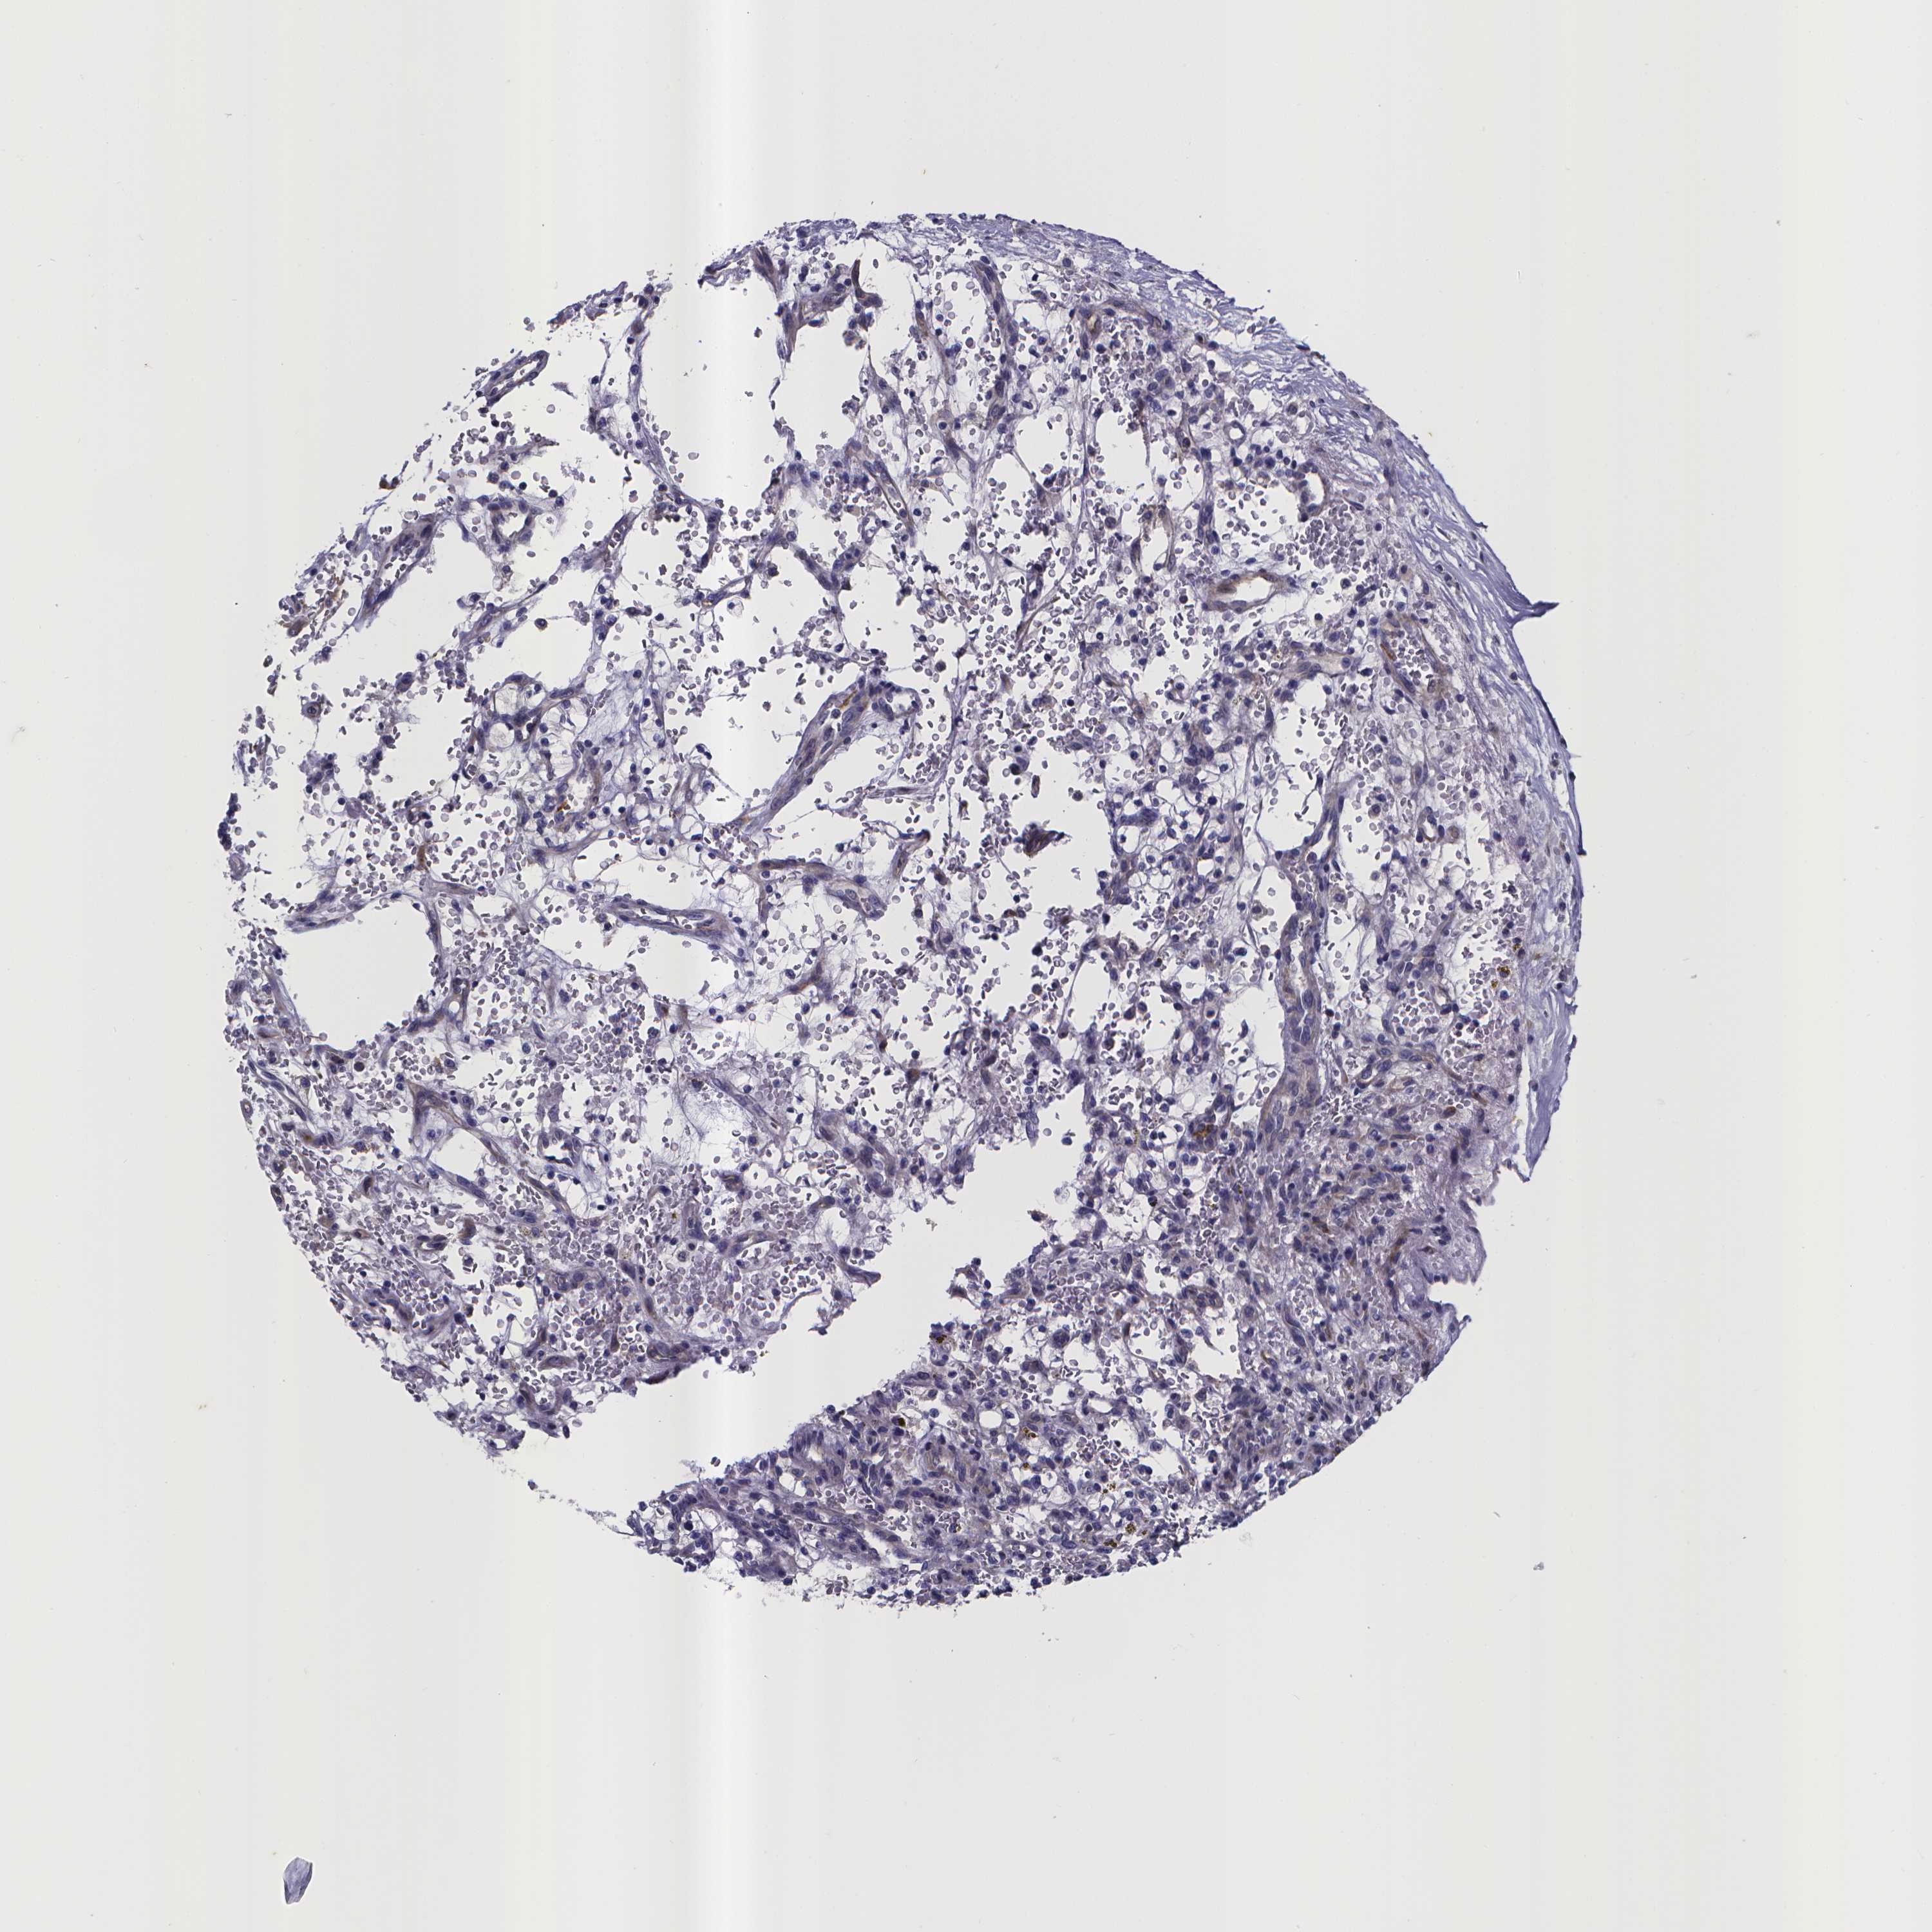

CANCER RENAL CANCER Show tissue menu

Renal cancer

Kidney chromophobe

KIDNEY CHROMOPHOBE (TCGA) - Interactive survival scatter ploti

RERG is not prognostic in Kidney Chromophobe (TCGA)